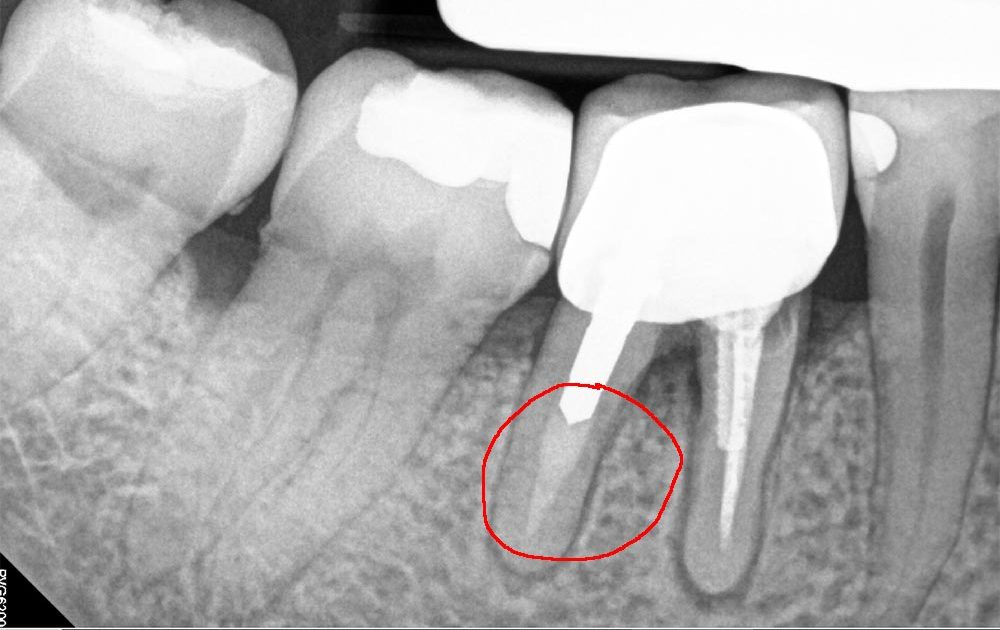

TIP: What to look for in root canal treatment?

When a root canal treatment procedure is carried out, it is of vital importance that the root canal of the tooth is adequately filled with gutta-percha. If a part of the canal remains empty (as on the image shown here), the infection can continue to develop inside the root and the bone, causing irreversible damage to the structure of the jaw, or lead to the need of tooth extraction.

If you had a root canal treatment done a while back, but you can still feel a foul odour from the area of the tooth contact our friendly receptionist staff to book an appointment.